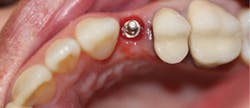

Figure 12: Final crown seating

A 1.8 mm x 14 mm Anew implant (Dentatus) was selected, and a surgical guide was fabricated for a flapless approach. In this instance, a healing cap was placed, and the existing flipper was relieved to address financial concerns (figures 9 and 10). A screw-retained crown was fabricated three months post insertion (figures 11 and 12). The patient reported no postoperative discomfort, and the case remains successful, as shown in the two-year postoperative x-ray (figure 13).